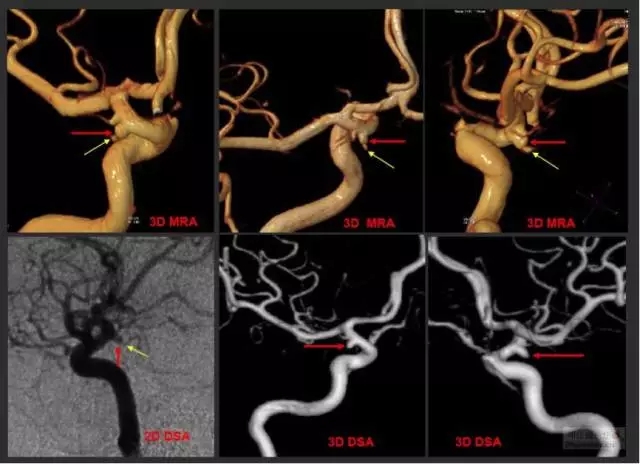

頭顱MRI(核磁共振成像):對于未出現動脈瘤破裂,僅以神經壓迫癥狀前來就診或無癥狀體檢患者具有重要診斷作用,特別是大動脈瘤,頭顱核磁共振能夠有效發現并且初步診斷;而核磁共振血管造影(MRA)可以在發現顱內可疑病變后用于確診是否存在腦動脈瘤,部分高場強核磁共振甚至能夠替代腦血管造影,作為一種無創的檢查方法收到越來越多的歡迎。

腦血管造影(DSA):診斷腦動脈瘤的金標準,可動態和三維重建了解動脈瘤的位置、形態、數目、大小,以及與周圍組織結構和周圍血管的關系,是決策下一步治療方案的主要依據。醫生最想知道的信息,包括腦動脈瘤的部位、形態、大小,都可以通過腦血管造影得到,并可以在明確腦動脈瘤的診斷后直接轉入對腦動脈瘤的治療。

CTA/MRA/DSA是確診腦動脈瘤的主要檢查手段